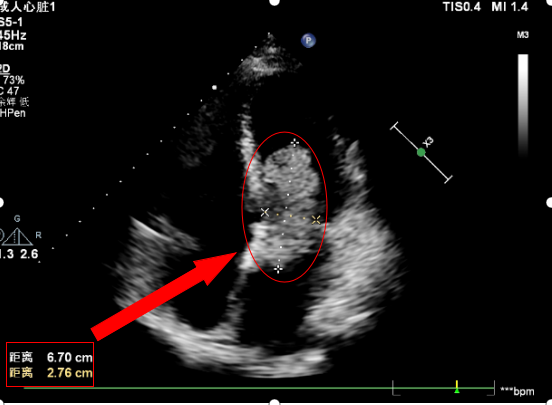

患者王先生,62岁男性。因“活动后胸闷、气喘1年”入院。多次就诊于外院,曾诊断为“慢性阻塞性肺疾病”,给予对症诊疗后症状未见明显好转。近期上述症状进一步加重,活动能力下降明显,并出现TIA,遂求诊于我院,门诊查心脏彩超示:左房粘液瘤,心脏瓣膜病,二尖瓣重度关闭不全,三尖瓣重度关闭不全,肺动脉高压,收入院后完善冠脉造影检查示:冠心病,前降支管腔重度狭窄,需同期手术治疗,且患者平素患有2型糖尿病,血糖水平控制不佳,进一步加大手术难度。左房粘液瘤,如同埋藏于人体内的不定时炸弹,随时威胁患者的生命安全。

(患者术前心脏超声,箭头处为心脏肿瘤)